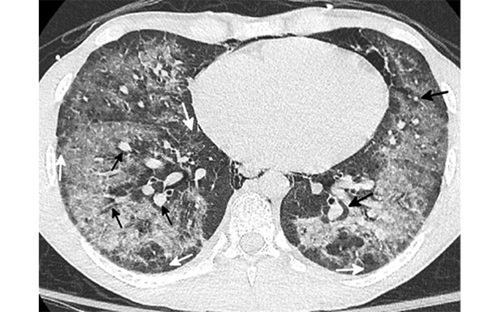

Axial CT scan in a 19-year-old man presenting to the emergency department in January 2021 with presumed COVID shows diffuse ground glass opacity with conspicuous subpleural (white arrow) and peribronchovascular (black arrow) sparing. A small amount of pneumomediastinum was present. Based on the pronounced peribronchovascular sparing in a young patient, an organizing pneumonia pattern of EVALI was suggested in addition to COVID related pneumonia. The patient admitted to vaping THC products multiple times a week and was negative for COVID on three consecutive PCR tests. He rapidly improved after steroid administration and was discharged from the hospital in two days.

Courtesy of Chest Journal: Kligerman et al, 2021; 160:1492-1511